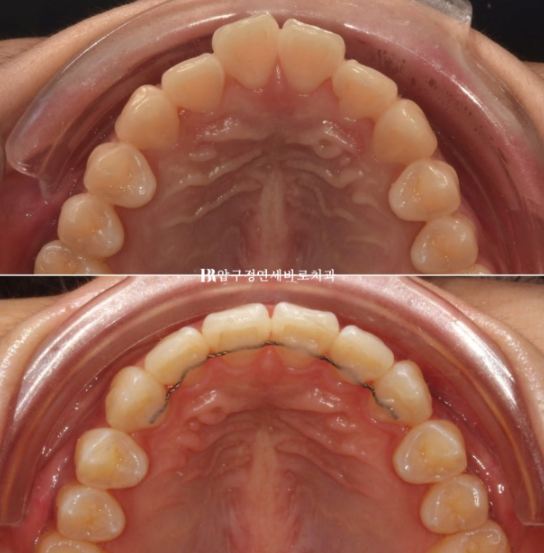

24년 3월부터 24년 4월까지 두달간 첫세트 7개의 장치를 다 낀 모습입니다.

24.04

앞니 배열은 97%정도 완료가 되었습니다.

미세하게 덜 돌아간 치아드로가 미세한 공간들을 마무리 하기 위해 추가제작 즉 재제작에 들어갑니다.